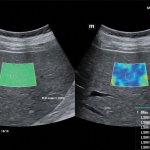

با توجه به اینکه دستگاه های جدید بررسی فیبروز کبد (سفتی کبد)بر پایه سونوگرافی میباشد،در مرکز تخصصی فیرواسکن دکتر شماعی ،فیبرواسکن کبد صرفا توسط پزشک متخصص رادیولوژی انجام میشود و علاوه بر انجام فیبرواسکن و ارزیابی فیبروز( سفتی ) کبد و تعیین میزان کبد چرب، سونوگرافی کبد و بررسی کیسه صفرا و مجاری صفراوی نیز بدون دریافت هزینه انجام خواهد شد

مرکز تخصصی فیبرواسکن دکتر شماعی جز محدود مراکزی در مشهد میباشد که انجام فیبرو اسکن با استفاده از جدید ترین دستگاه ها انجام میگرد و تمامی مراحل انجام فیبرواسکن و تجزیه و تحلیل اطلاعات و گزارش فیبرواسکن توسط پزشک متخصص صورت میگیرد.

با توجه به اینکه نتایج فیبرواسکن کبد نقش تعیین کننده در درمان کبد چرب دارد،لذا این مرکز متعهد به انجام فیبرواسکن کبد توسط پزشک متخصص و با صرف وقت لازم میباشد